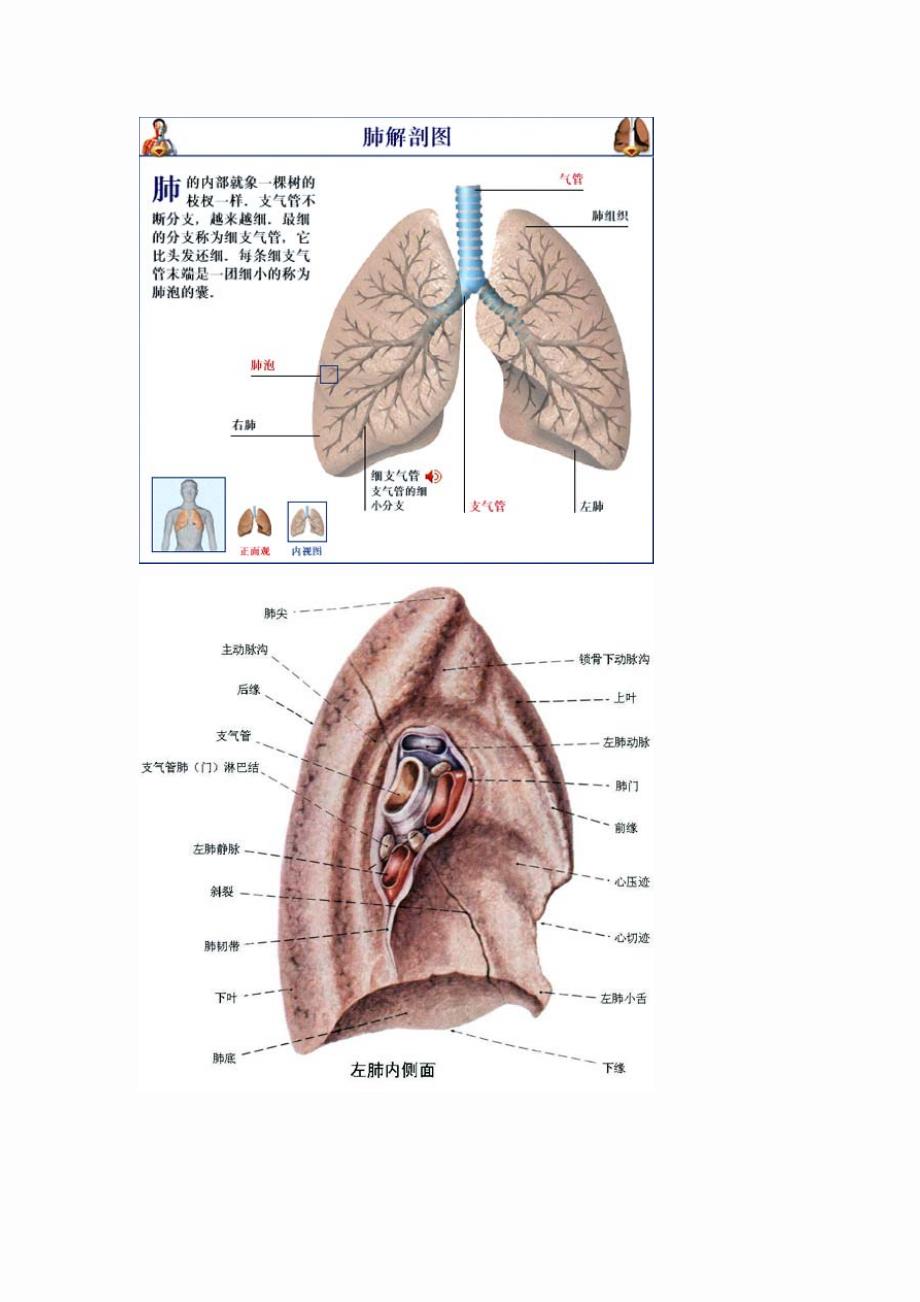

肥的分叶和分段#肺分叶分段 #医学科普 #肺部健康 cr. - 抖音

第四节 肺尖 肺 肺尖 肺底(膈面) 肺的外形 前缘 下缘 肋面 内侧面

好漂亮的肺部解剖!

肺部的解剖结构1

肺段分解 - 美篇